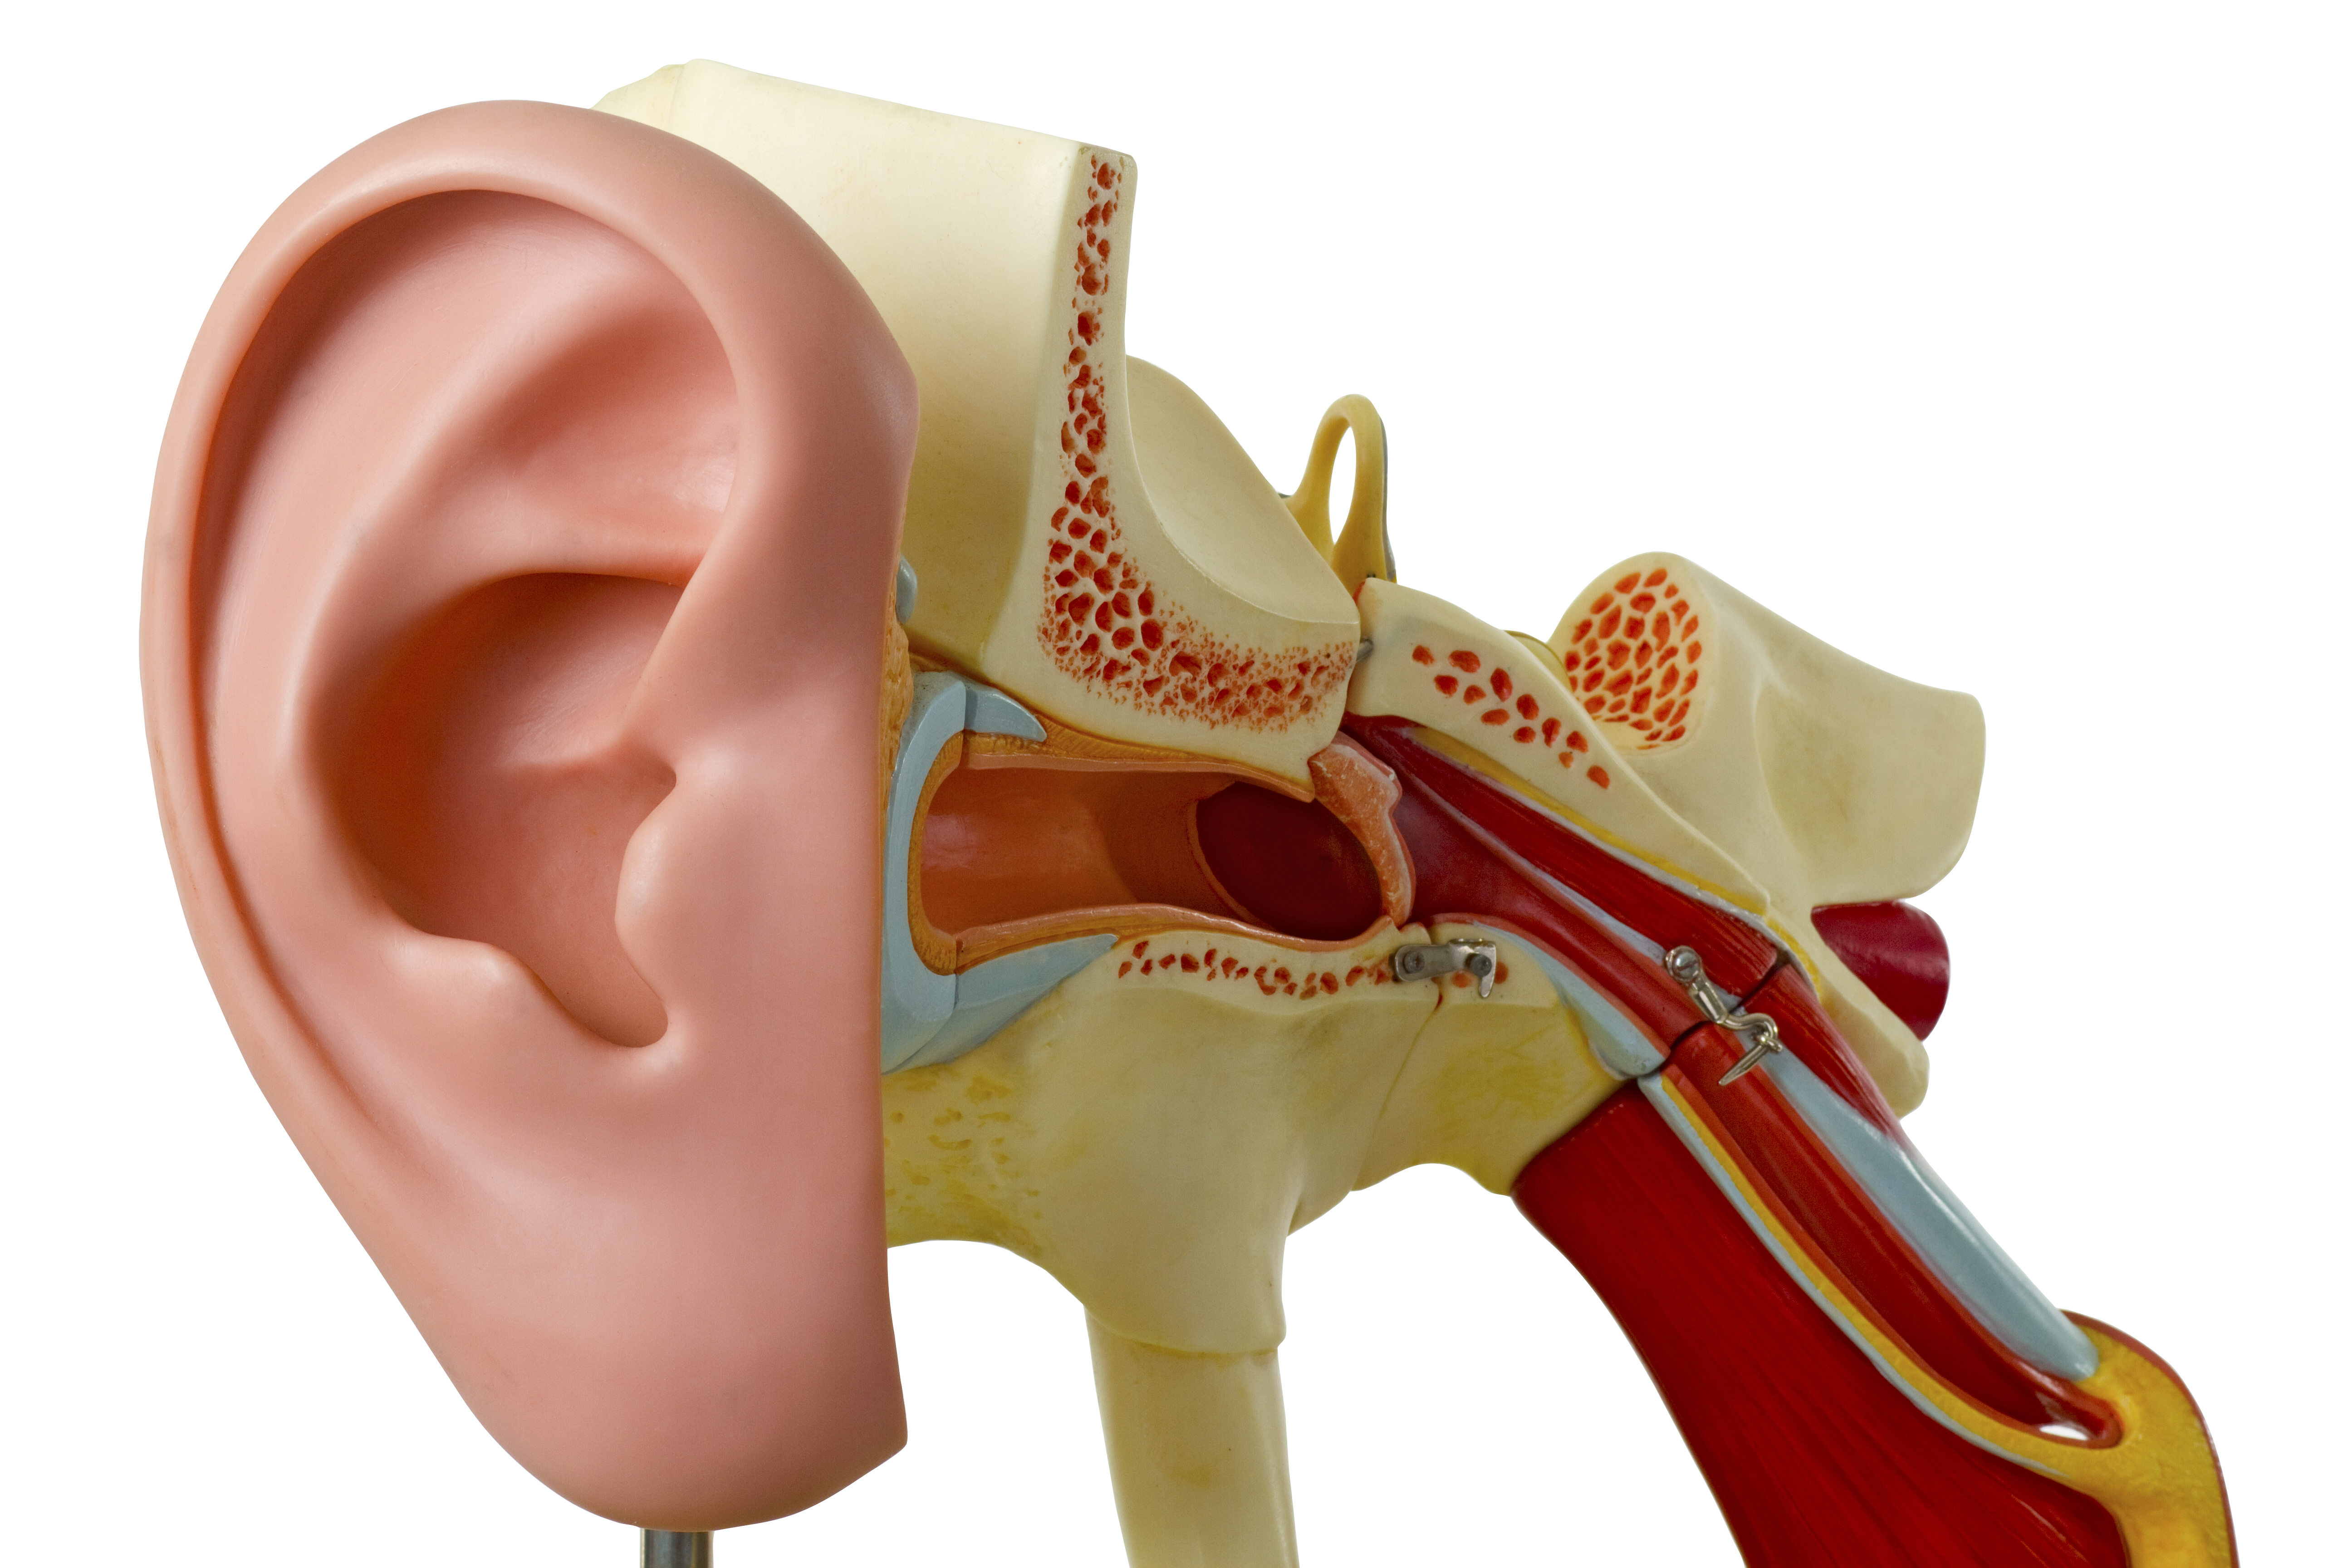

Современные слуховые аппараты при сенсоневральной тугоухости